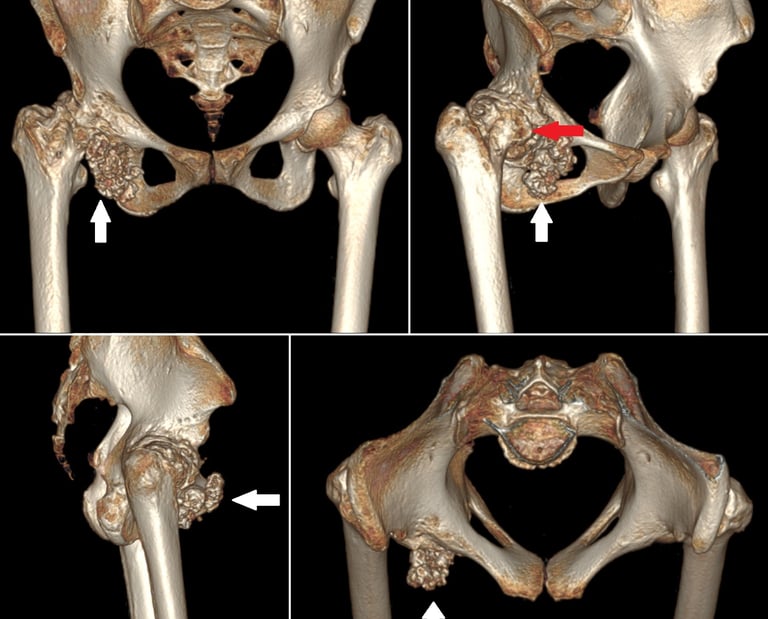

Giant synovial chondromatosis of hip

Synovial chondromatosis is a rare, benign condition occurring due to metaplasia of synovium leading to cartilaginous nodules, which may mineralise, break free to form loose bodies or even ossify. The aetiology still remains unknown. It usually involves the knee joint, and very rarely involves the hip. It usually occurs in the third to fifth decades of life and is more common in males. The clinical presentation is usually of pain, swelling and restriction of movements of the joint involved. Radiographs, CT and MRI can diagnose the condition in most cases. We discuss a case of giant synovial chondromatosis of the hip presenting with secondary osteoarthritis of the hip joint.

Myositis ossificans is a benign ossifying lesion which can affect any soft tissue including subcutaneous fat, tendons, muscles and nerves. The common locations include the elbow, hip and knee. The pelvis is an extremely rare site for myositis ossificans which has only been described anecdotally in the past. Myositis ossificans involving the adductor muscles- adductor longus or adductor magnus is also an uncommon location, with only a few case reports of its occurrence in athletes. Myositis ossificans involving the adductor longus has been reported to occur in the form of a long, slender, pencil shaped ossification, however the inverted horn is being reported for the first time.